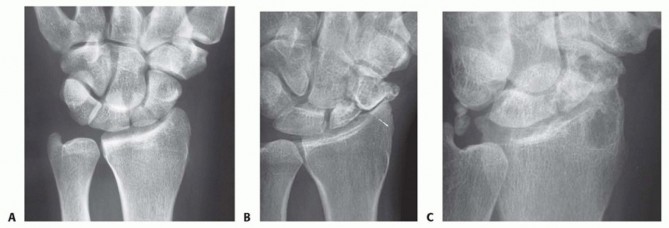

FIG 2 • A. Early radiographic appearance of scaphoid nonunion before degenerative change. B. Development of degenerative changes at the radial styloid-scaphoid interface. C. Advanced changes involving the entire scaphoid fossa. Magnetic resonance imaging (MRI) is useful in evaluating the scaphoid for vascularity, although definitive determination of avascularity may be difficult. Although contrast-enhanced MRI has shown improved sensitivity over noncontrast studies in detecting AVN, it may not be effective in detected AVN in up to 25% of cases.